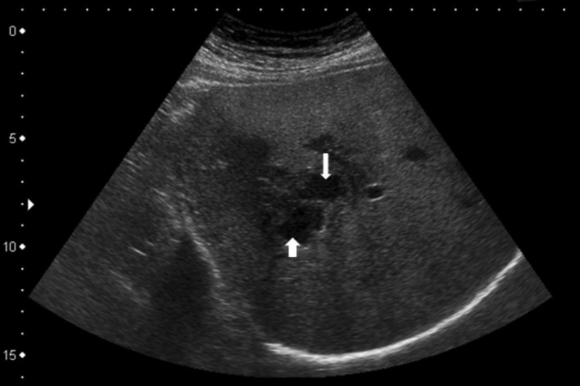

Kết quả xét nghiệm của các bệnh nhân dương tính với bệnh sán lá gan lớn. Hình ảnh siêu âm cho thấy có ổ áp xe ở gan kích thước ở cả 2 thai phụ.

Hình ảnh sán lá gan lớn qua siêu âm (Ảnh: BV).